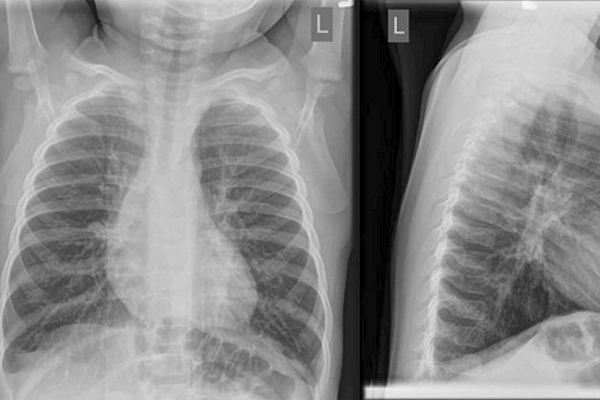

“Ordering a chest X-ray is often meant to give peace of mind for families and care providers, but the reality is that in typical cases this extra measure could actually do more harm than good,” says Dr. Friedman. “It’s not just exposure to unnecessary radiation, but also the increased likelihood of mistaking the typical X-ray changes seen in bronchiolitis, and making an incorrect diagnosis of bacterial pneumonia with the unnecessary use of antibiotics that can follow.”

According to the article, guidance to avoid imaging is originally based on studies showing that likely <1 per cent of X-rays will result in a new diagnosis. Despite this, a recent study of children seen in 38 paediatric emergency departments across eight countries in North America, Europe, and Australasia by Dr. Amy Zipursky from the SickKids Emergency Department, found that chest X-rays had been performed in 23 per cent of previously healthy infants aged 2-12 months with bronchiolitis not requiring intensive care, and that this was associated with antibiotic use irrespective of disease severity.